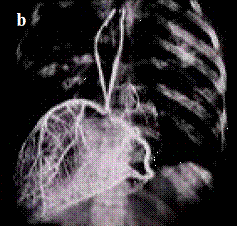

Figura 5. Arterele coronare - piese anatomice injectate cu substanta de contrast si radiografiate: a) in vitro; b) la cadavru